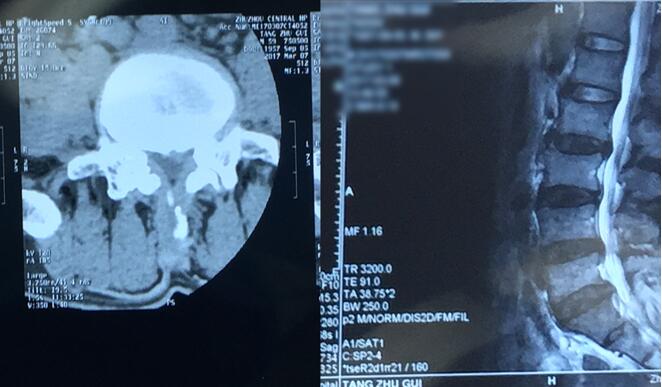

入院后,脊柱科湯偉副主任醫(yī)師詳細(xì)了解唐師傅的病情,根據(jù)腰椎磁共振、CT等檢查結(jié)果,發(fā)現(xiàn)唐師傅多節(jié)段腰椎間盤突出,且L4/5節(jié)段突出最多,引起患者典型的神經(jīng)根受壓癥狀,屬于責(zé)任椎間隙,明確診斷。且了解到唐師傅的家庭情況后,脊柱科醫(yī)生團(tuán)隊決定盡早為他安排手術(shù)。

唐師傅腰椎影像學(xué)檢查